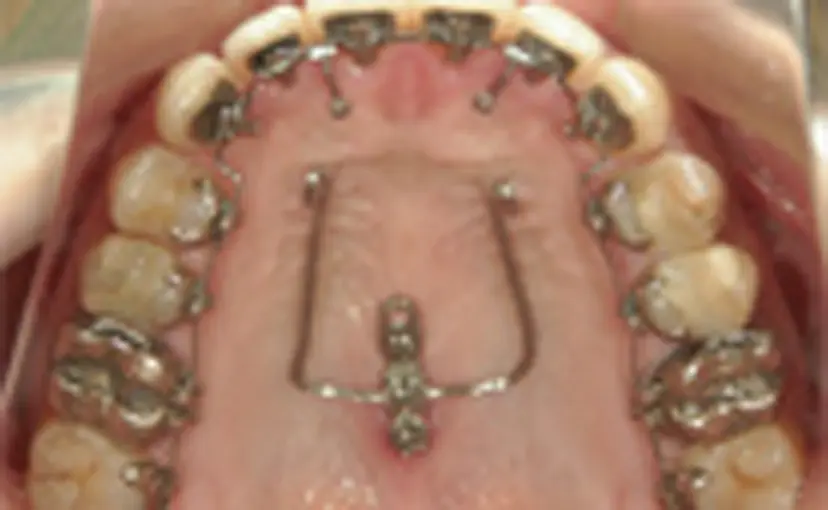

主に舌側矯正の場合に使用し、口蓋の部分に埋入します。2本のアンカースクリューとその上に土台となるプラットフォーム、さまざまな方向に歯の移動を行なうワイヤーからできています。ガミースマイルや下顎が奥へ引っ込んでいるケースの改善に使用します。費用はシステム全てで99,000円(税込)になります。